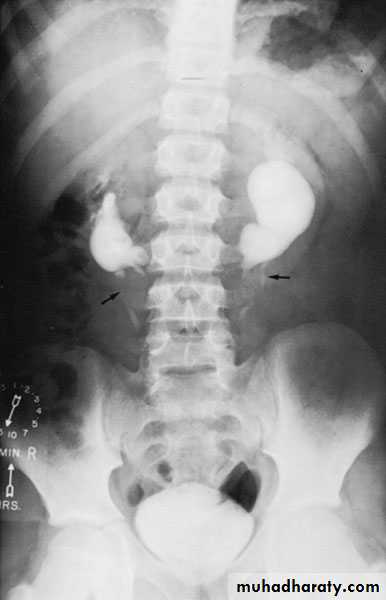

Cystic disease of the kidneysPolycystic kidney disease :

Congenital cystic kidney (polycystic kidney) (Adult cystic renal disease)

Autosomal dominant, transmitted by either parents, 50% of offspring affected.

Both kidneys replaced by large no. of cysts of variable size which make the kidney of large size.

The cysts contain clear fluid but sometimes blood.

The cysts progressively increase in size causing pressure atrophy of the renal parenchyma and pressing the ureter.

15% associated with cystic disease of liver, lung, pancreas or spleen.

Diagnosis: Family history of polycystic disease.

U/S, IVU, CT scan, MRI